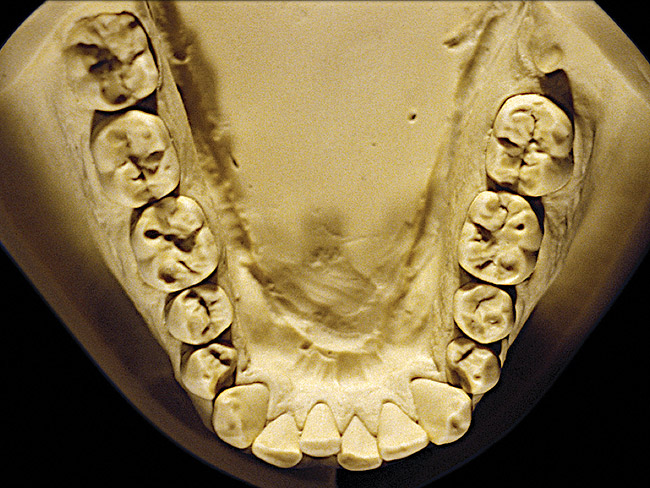

Figure 12  Advanced NCLTS from toothpaste, mandibular arch.

Figure 12

Figure 7 and Figure 8 are examples of NCLTS resulting from toothpaste. Upon examination, one could see that the overall anatomical detail of the teeth was faded with a sandblasted appearance. A closer view of the facial surfaces (Figure 9 and Figure 10) illustrates this to a greater degree and one can observe that the normal intricate facial anatomy was completely missing. It is interesting to note there was no cervical recession of the gingiva, even though every surface of every tooth had been abraded. This is due to the fact that this patient had always used a soft, round-ended filament toothbrush.21-22 This patient's sole desire regarding her oral hygiene was to get her teeth whiter.

So that the previous example is not misleading, the behavioral profile of the toothpaste abuser is not necessarily the "caries-free immaculate oral hygiene patient," but can be virtually anyone who brushes their teeth with toothpaste. Figure 11 and Figure 12 illustrate a more advanced example of toothpaste abuse showing a patient with multiple restorations and some unkempt teeth. The anatomical details were faded with a sandblasted appearance and the silver alloy restorations were highly polished. The facial surfaces of the mandibular canines and premolars were affected the most, creating the pathognomonic pattern. Figure 13 and Figure 14 are a close-up view of this area, illustrating a cupping or cratering effect, but of the asymmetrical variety. This patient did not like the color of his teeth and spent an inordinate amount of time brushing his teeth. Again, likewise due to the exclusive use of a round-ended, soft-bristle toothbrush, note there was no cervical gingival recession in this case either. When the featured casts illustrating toothpaste abuse (Figure 7, Figure 8, Figure 9, Figure 10, Figure 11, Figure 12, Figure 13 and Figure 14) were hand-articulated, the worn surfaces did not match up and the diagnosis of toothpaste abuse was confirmed.